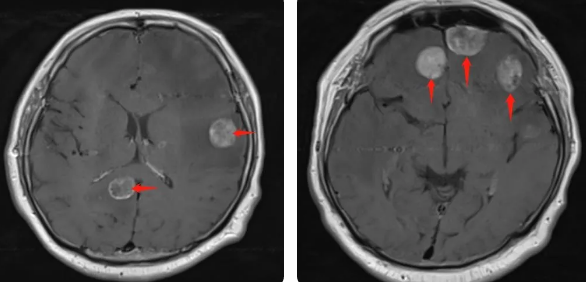

無(wú)獨(dú)有偶,60歲的左肺癌患者石先生,在外院接受了手術(shù)治療,結(jié)果術(shù)后10月出現(xiàn)腫瘤腦轉(zhuǎn)移,頭部增強(qiáng)MRI顯示:顱內(nèi)多發(fā)占位性病變伴水腫,接二連三的重?fù)糇屖壬霈F(xiàn)表情淡漠,沉默寡言,絕食等抑郁癥狀,VMAT放療技術(shù)與心理疏導(dǎo)雙管齊下,3周的治療后顱內(nèi)轉(zhuǎn)移病灶顯著縮小,部分甚至消失,困擾石先生的頭痛、頭暈癥狀也不復(fù)存在,石先生重拾對(duì)生活的希望,也對(duì)未來(lái)的治療充滿信心。